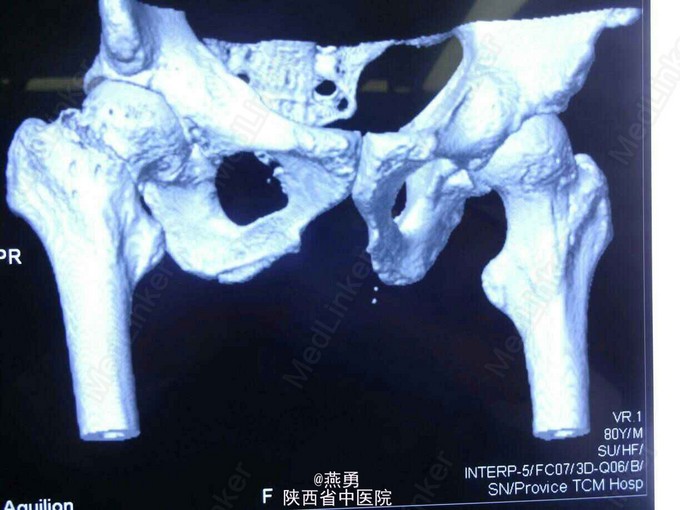

81岁男性患者,一个月前不慎摔倒右髋部着地,当即右髋部疼痛,活动困难,被动活动疼痛明显加重,近来患者自觉疼痛无缓解,活动受限,遂到我院就诊。 患者五年前曾在其他医院行结肠癌根治术 。

右下肢外展外旋畸形,较健侧短缩1CM,右髋关节肿胀不明显,压痛(+), 右腹股沟中点压痛(+),右下肢纵轴叩击痛(+)。

诊断:右股骨颈骨折,骨囊肿待查。治疗:右侧人工股骨头置换术,病灶清除探查术。麻醉生效后,常规逐层切开及暴露可见股骨颈颈中型骨折,清除周围纤维增生挛缩及瘢痕组织,取头器取出断裂的股骨头,患肢内收外旋脱位后,截骨,髓腔开口及扩髓,探针可见小转子内测约0.5*0.8cm病灶空腔,内壁完整,刮除腔内病灶送病检,填入少量抗生素型骨水泥,装入生物型股骨柄,置入双动头股骨头假体,复位,见右侧髋关节屈伸旋转活动良好,未出现脱位,双下肢等长。冲洗,清点纱布器械后,放置引流,关闭伤口加压包扎。 术后安返病房行预防感染预防血栓及对症治疗。